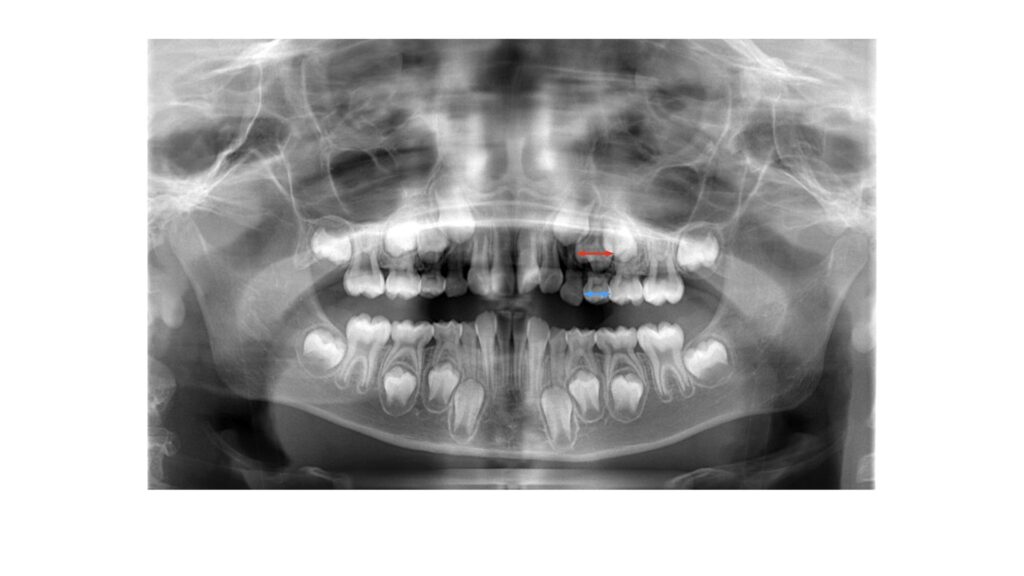

例①「このレントゲンを見れば“隙間がゼロ”。矯正が必要です」

「青矢印が乳歯」、「赤矢印が永久歯」「こんなに歯は大きくなるのに収まると思いますか?顎も小さいし。」「今すぐ始めないと間に合いません!」「6歳までが勝負です!」

このような治療の勧め方をされた場合には最大限注意しましょう。

- ポイント:パノラマX線は“サイズ測定に不向き”。拡大率や歪みが部位で異なり、歯の実寸やスペース量の確定には適さない。

以下にさきほどのレントゲン写真のお子様の乳歯と永久歯の大きさの違いを本人の歯の写真で見ていただきます。

青矢印が乳歯、赤矢印は永久歯です。写真も倍率の違いや撮影アングルによって見え方は異なりますが参考にはなります。

「レントゲンでは乳歯の方が永久歯よりも大きく見えていた」のが実際は「乳歯の方が永久歯よりも大きい」のです。

実は永久歯の方が乳歯よりも大きくなるのは前から数えて1〜3番目の永久歯までです。4番目、5番目に関しては永久歯の方が乳歯よりも小さくなるのです。